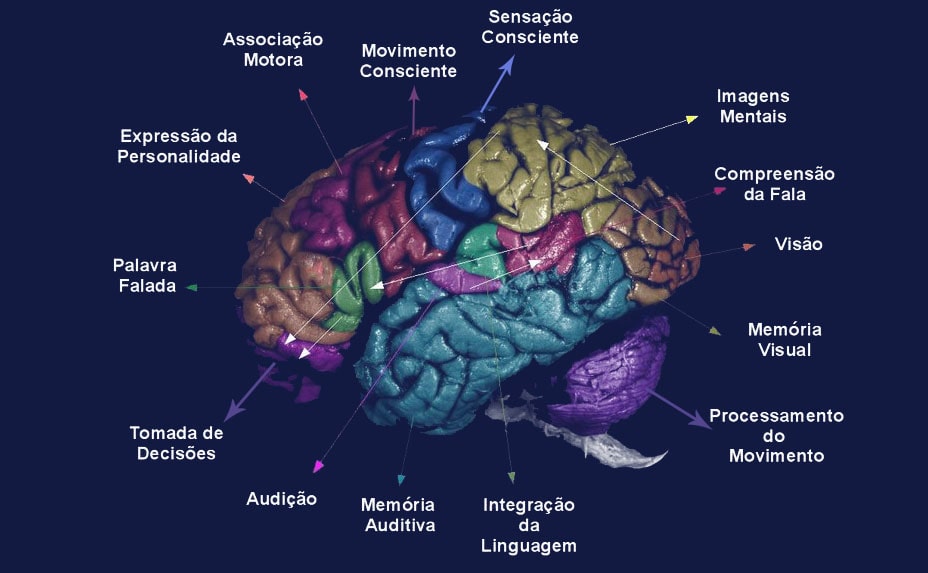

Dislexia

Definição, causas e...

Reconhecimento de...

O cérebro...

Básico em Inteligência Emocional

Mente e cérebro...

Raciocínio consciente...